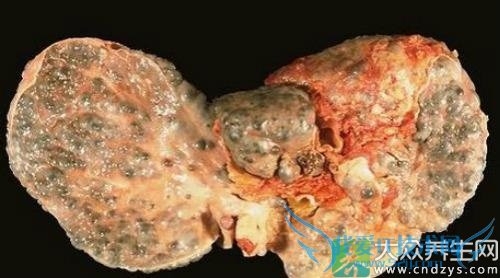

重度脂肪肝吃什么好

重度脂肪肝吃什么好

重度脂肪肝属于脂病的一种.显然的引发这个病着的原因是包含很多的.特别是在男性居多.因为男性多由于吸烟喝酒也会造成重度脂肪肝的形成,此外还有其它的在原因.但不管是什么样的原因造成的,患了重度脂肪肝的都有关心的一个问题是,患了这个病平时可以吃什么好一点呢,那么什么样的食物吃了对重度脂肪肝患者有帮助的呢.